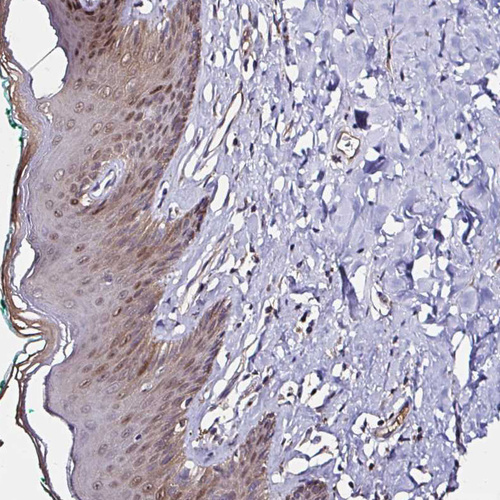

Immunohistochemistry analysis in human colon and skeletal muscle tissues using HPA055752 antibody. Corresponding TXN RNA-seq data are presented for the same tissues.